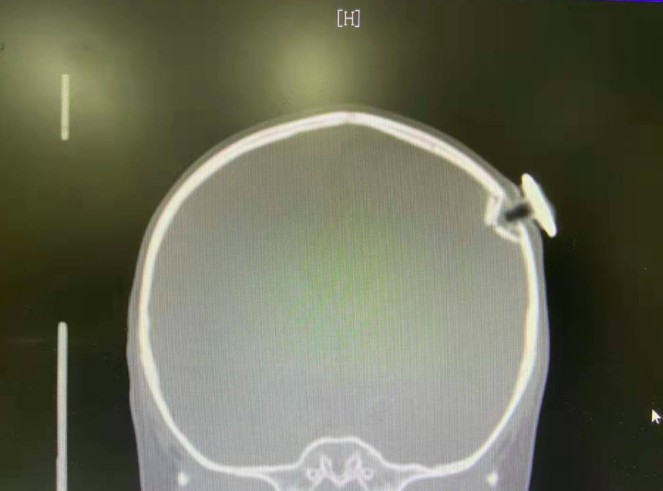

患儿头部的“星星”磁力钉。 本文图片均为上海市儿童医院供图

影像学检查结果显示,磁力钉插入颅内

根据CT检查显示

这枚磁力钉撞碎了孩子颅骨

扎进大脑约1.3厘米

造成左侧顶骨凹陷性骨折和脑外出血

而且刺破脑膜

差点就损伤了脑部的功能区